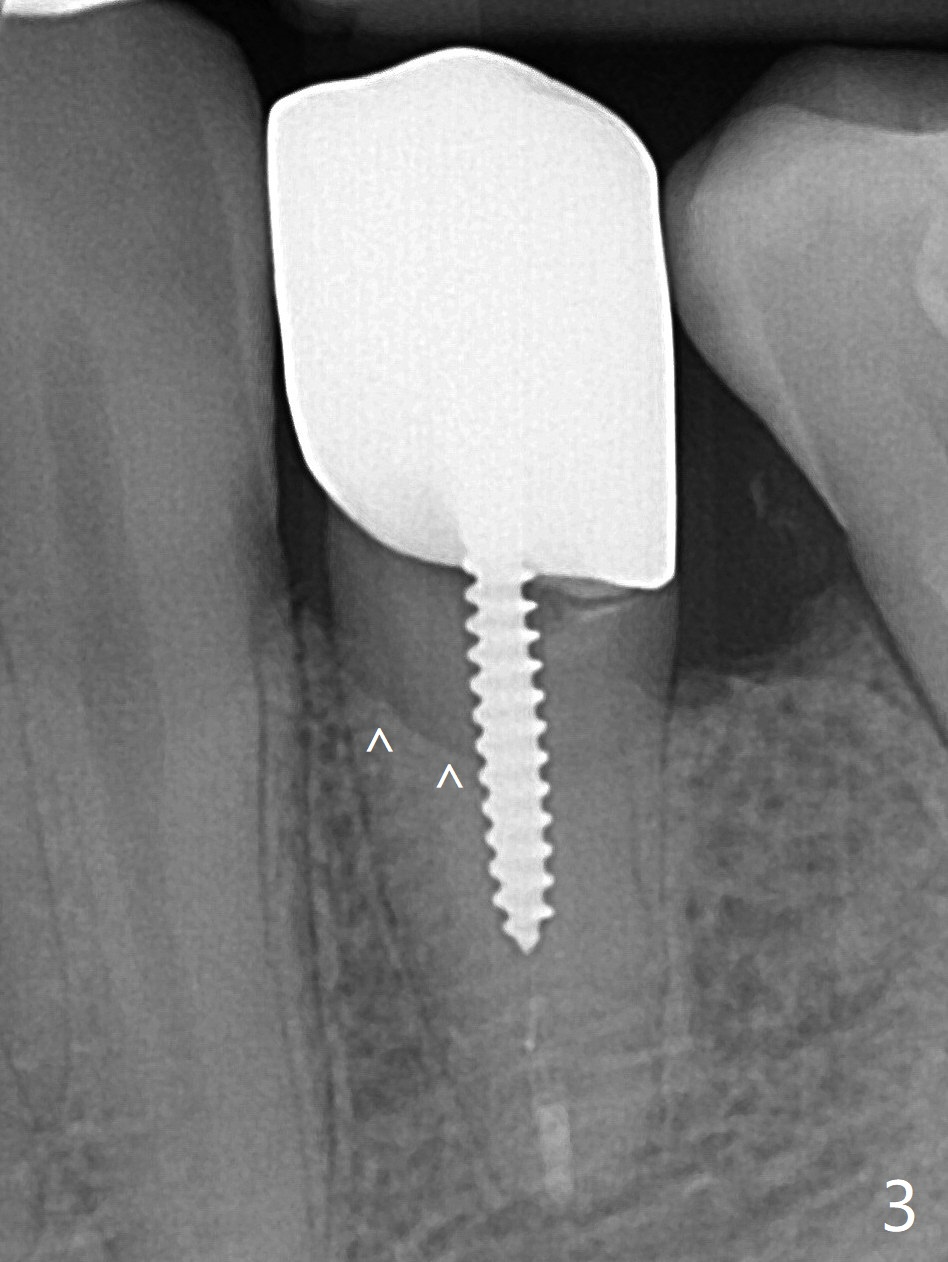

A 42-year-old man has been our patient for 3-4 years (Fig.1). An asymptomatic fistula develops lingual to the tooth #21 (Fig.2). An oblique fracture line appears to be next to a post (Fig.3 ^). A 3.5x11.5 mm implant seems to be able to be placed immediately lingual to the thick lingual plate with guide (Fig.4 L). No buccal deviation will occur with sufficient buccal gap. Design of an immediate implant at #21 (coronal section, Fig.5). In fact the root remains in place first (i.e., extract the crown first, Fig.5'). When osteotomy is done with the last drill 4x11.5 mm, there will be no deviation because of even counteraction between the buccal root and the lingual plate (Fig.6'). Then the root will be removed. But the 4.5x11.5 mm implant may be deviated buccal because of implant engagement into the lingual plate without buccal counteraction. Therefore, a 4x13 mm implant will be placed following 3.5x13 mm (last) drill. The implant is placed between the mesial and distal walls (Fig.7 sagittal section).